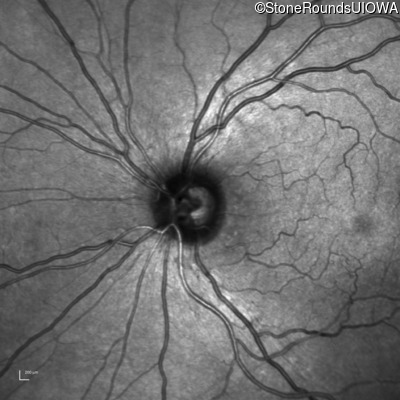

Infrared Fundus Photograph - Right - 20/400 sc

Exemplar